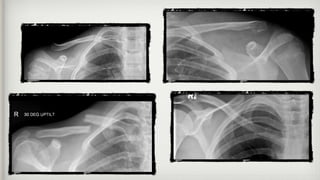

What do they look like on X-

ray?

What do theylook like on X- ray?